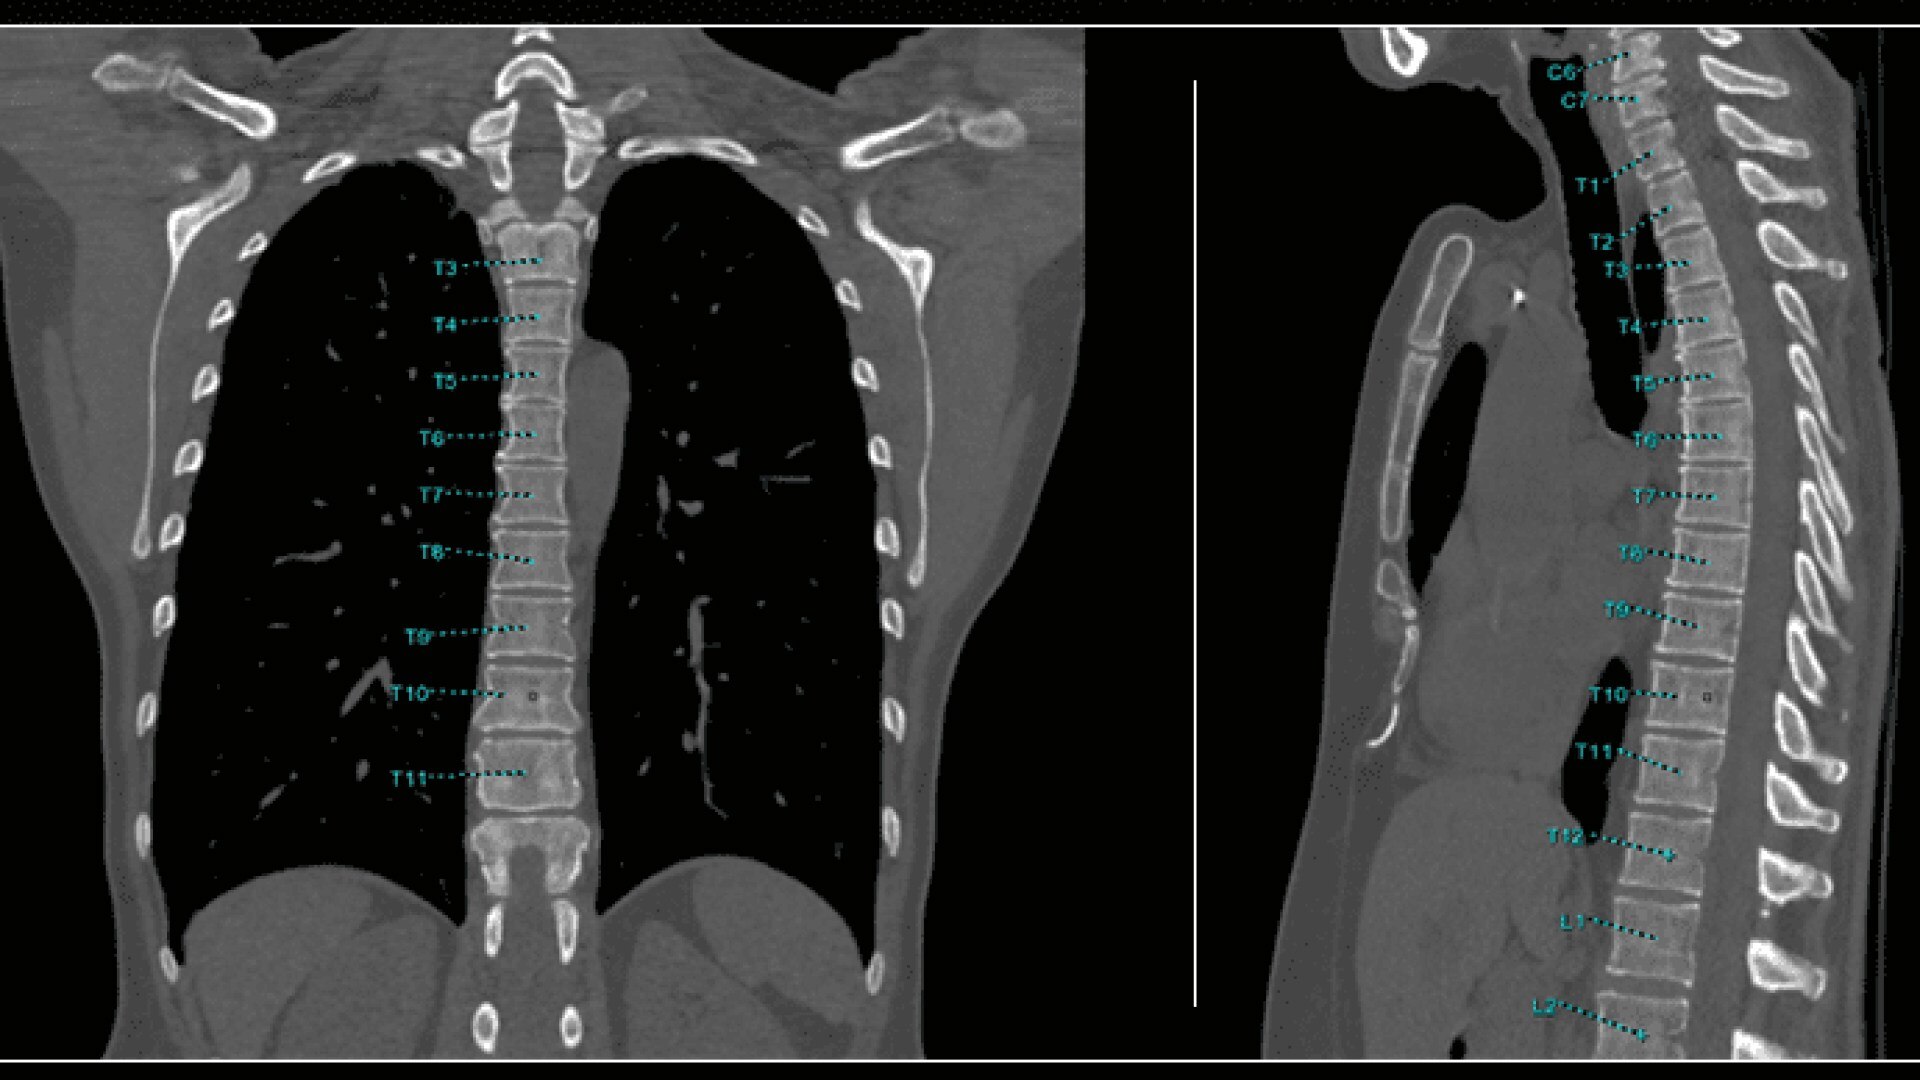

Bone VCAR

Spine assessment with deep-learning based CT application.

Automated spine identification and labelling.

>90% labeling accuracy based on Deep learning algorithm trained on global datasets acquired with a broad range of acquisition parameters.

• Automated spine labeling

• Works on full spine acquisitions as well as limited acquisitions containing segments of the spine